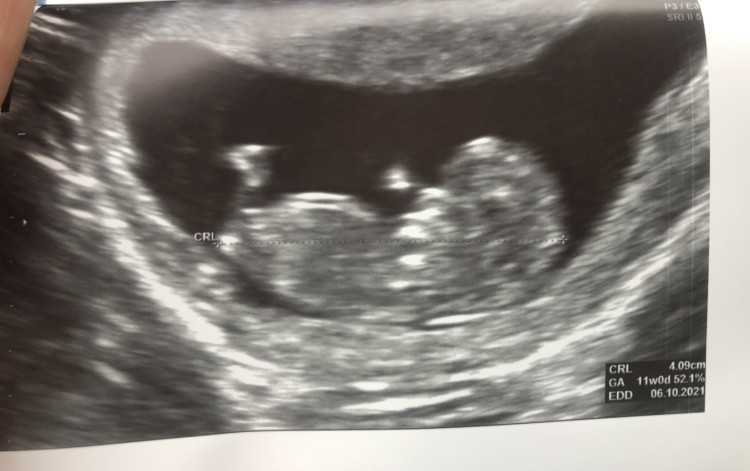

A ja psychicznie nie wytrzymałam z moim bólem brzucha i pojechałam na usg.

Okazało się, że dzieć starszy o dwa dni. I wszystko jest ok.

Teraz brzuch może boleć

CRL 4cm

FHR 163

11+0